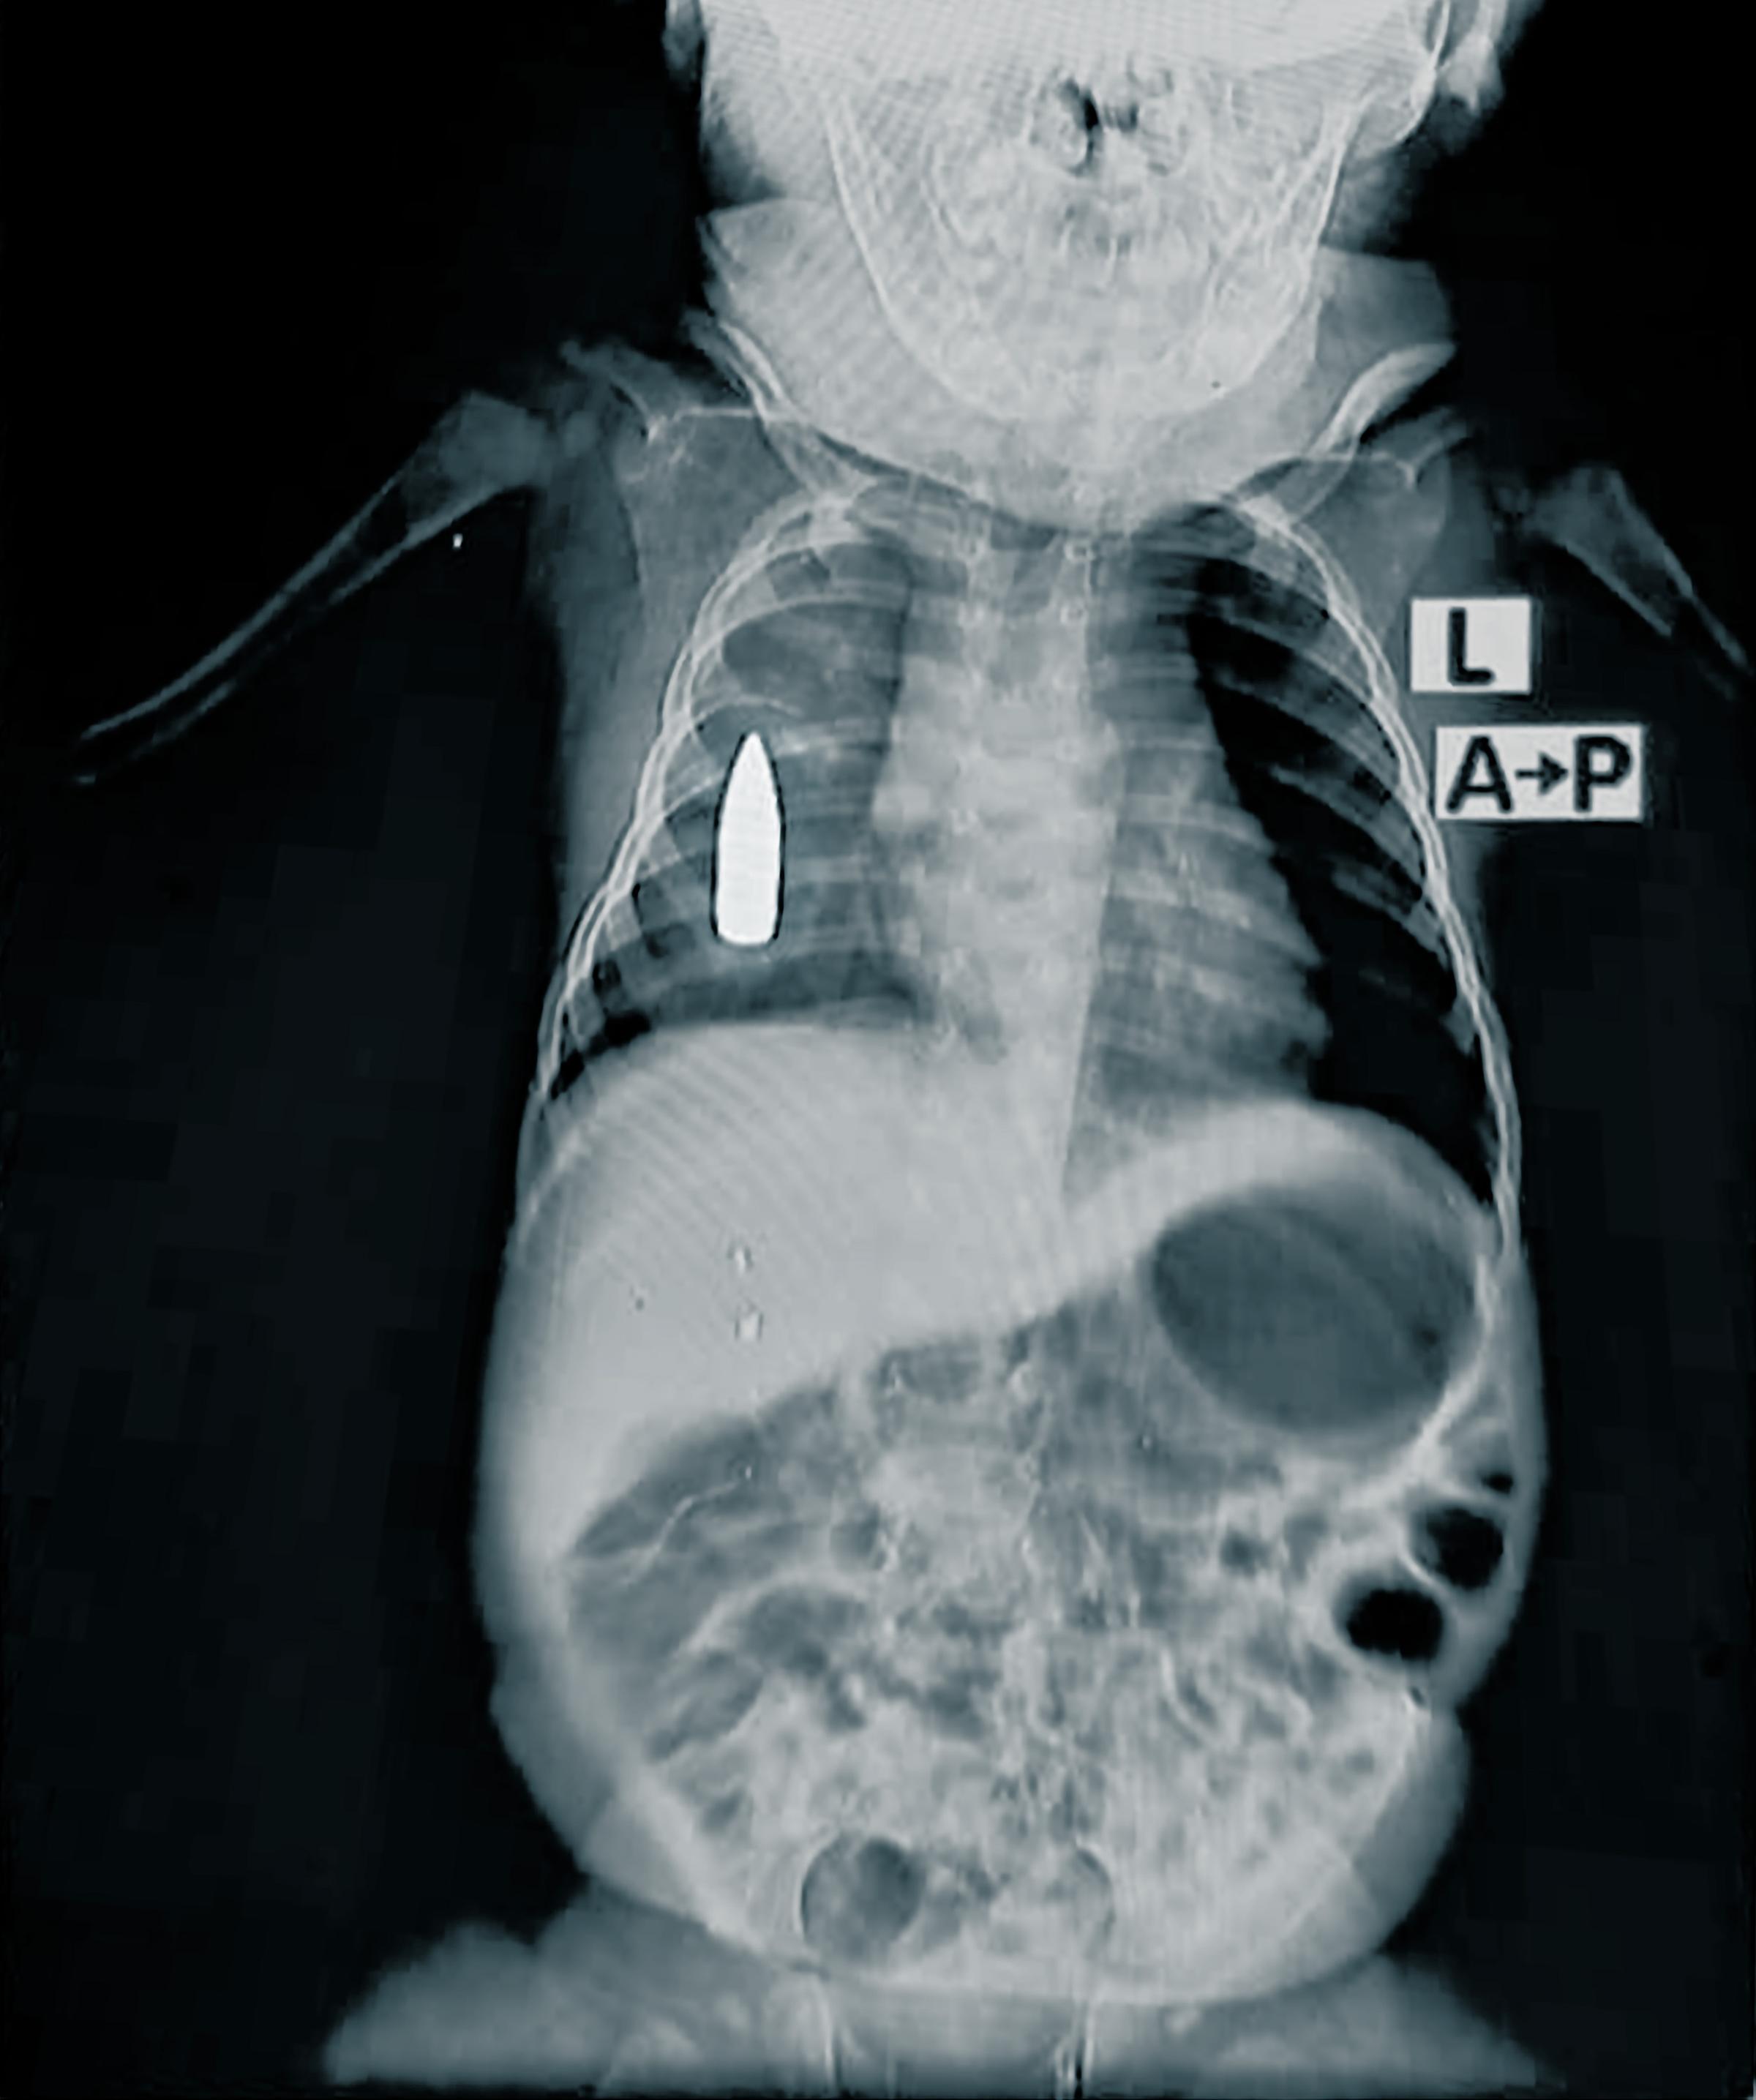

“18-month-old baby Riyad was brought to the emergency room after a stray bullet struck his right side while he was napping in his family’s home,” said Dr Moeen*, MSF medical team leader.

“The medical team fought for four hours to stabilise him. Due to the heavy loss of blood, the chances of him surviving the surgery were fifty-fifty.”

The team was able to stop the bleeding however the bullet remained lodged in his chest. It is unclear how long it will be before anything can be done about this. The hospital does not have advanced surgical capacities, partly as a result of a systematic blockage on sending surgical supplies since October 2023. Referring patients out of area is also very difficult as transport routes are either destroyed or far too dangerous.

Riyad is one of the 314 children treated for gunshot and blast wounds in 2024.